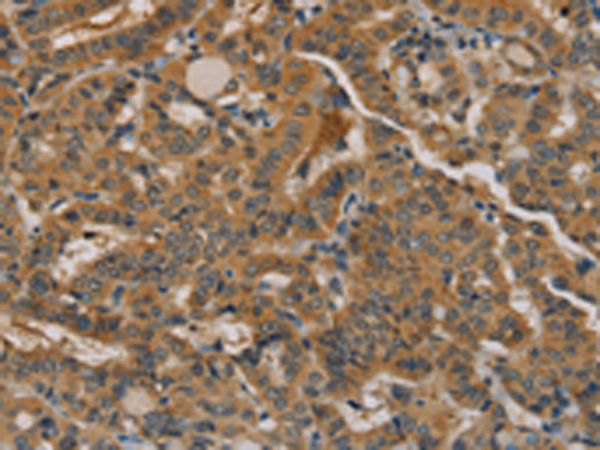

分类: 科研抗体货号: P08540别名: NOS2; ZC2HC12B应用: IHC反应种属: Human